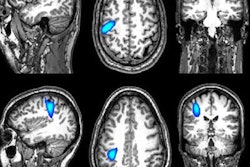

In other news, a group from the U.K. presented a prototype magnetoencephalography (MEG) scanner capable of capturing 3D brain images of adults and children while they perform simple tasks. The MEG helmet could pave the way for a better understanding of brain development and various neurological conditions, the group said.